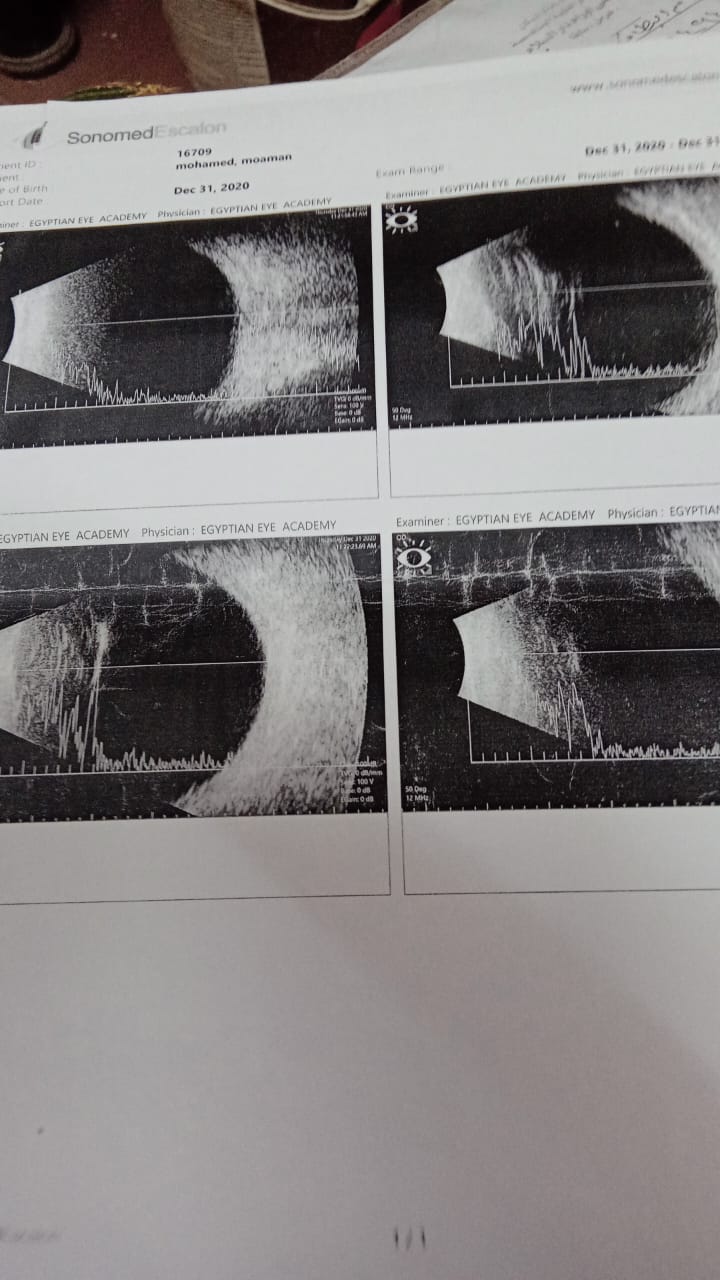

وقعت آلة حادة على عين مؤمن، تسبب في انفجارها، خلال عمله بالأسقف المعلقة، كان الصغير لم يتجاوز حينها الـ 14 عامًا.

بدأت رحلة الأم بنجلها منذ 6 سنوات، وأجرى العديد من العمليات الجراحية، وتمكن الأطباء من تركيب أكثر من مرة قرنية له، إلا أن صلاحية القرنية لن تدوم طويلًا.

تستكمل الأم: ركبنا أول قرنية، وكانت كويسة وناجحة، لكن وقع من على السلم، والقرنية باظت، بعد كده ركبنا عدسة وبعد سنة ونص من نجاحها فشلت.

خلال تركيب العدسة الثالثة، أجريت العملية الجراحية بـ 25 غزرة، مما أدى إلى شعور مؤمن بصداع شديد، مع تورم العين، ونتيجة لذلك أصيبت العين بقرحة، حتى فشلت العدسة الثالثة.